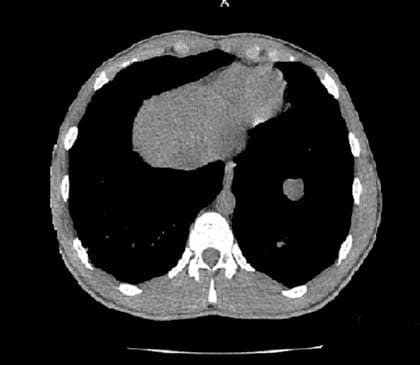

Рисунок 1. Метастатическое поражение легких тестикулярной герминогенной опухолью.Из анамнеза: новообразование заметил почти 10 месяцев назад, за медицинской помощью не обращался. С течением времени образование увеличивалось в объеме, появились субфебрильная температура, кашель. При обследовании по месту жительства выявлено образование правого яичка с метастазами в легких (согласно рентгенограмме). Пациент направлен в РНПЦ ДОГИ для дообследования и лечения.

Согласно данным функциональной и лучевой диагностики, онкологический процесс имел распространенный характер с поражением головного мозга, обоих легких, печени, селезенки, обеих почек.

Рисунок 2. Поражение правой тестикулы злокачественной герминогенной опухолью.Учитывая типичную локализацию опухоли и высокий уровень онкологических маркеров (бета-хорионический гонадотропин, лактатдегидрогеназа), гистологическая верификация не проводилась, была начата незамедлительно полихимиотерапия. После 2 курсов платиносодержащей полихимиотерапии — замедленный клиренс онкомаркеров, что привело к интенсификации терапии курсами полихимиотерапии 2-й линии.